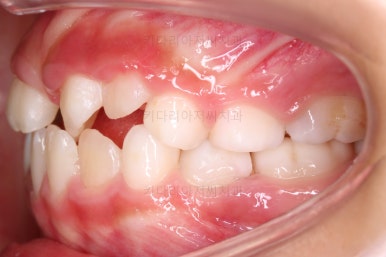

치료가 도저히 불가능한 유치는 발치를 하고, 대신 영구치가 나오기까지 매우 오래 걸릴 것으로 예상되어서 주위 치아들의 위치가 잘 유지되라고 공간유지장치를 해줬어요.

전문 용어로 band&loop라고 하는 이렇게 해줘야 추후에 또 다른 더 큰 문제가 생기지 않는답니다.

제 시기보다 한참이나 먼저 빠진 유치는 치아 공간유지장치를 꼭 염두에 두세요.